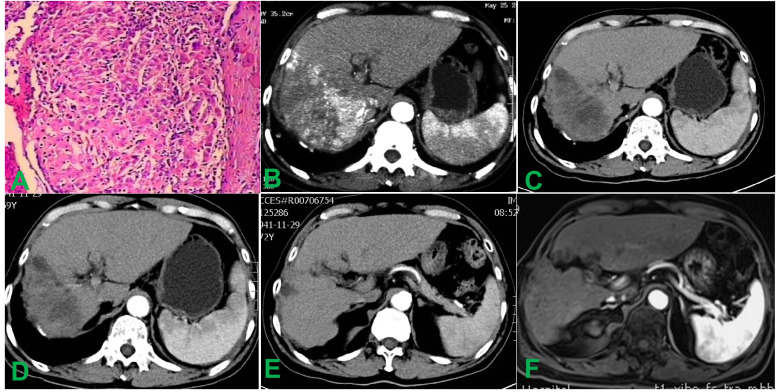

诊断评估:影像学检查显示肿瘤位于肝第Ⅶ、Ⅷ段,大小约14×12×10 cm。甲胎蛋白(AFP)为2107 ng/ml,右支肝静脉内可见HVTT。双肺可见多发弥漫性结节。BCLC分期为C期。肝脏穿刺病理活检确诊为HCC(图1,图2)。

图1. 治疗前后的组织病理学及腹部影像学检查结果。(A)活检标本的组织病理学分析证实为HCC。(B)术前增强CT示右肝叶内有一14.0×12.0 cm的肿块,伴有右肝HVTT。(C)术后4周增强CT示病灶内明显低密度,肿瘤缩小至10.0×6.0 cm,强化基本消失。(D)术后12周增强CT示肝脏肿瘤无强化,符合完全坏死,肿瘤缩小至9.3×5.7 cm。(E)术后3年随访影像示肝内肿瘤及瘤栓几乎完全消退,仅存少量无强化组织。(F)术后10年增强MRI证实肝内病灶持续稳定,无新发或复发。

治疗后第4天和第7天AFP、白蛋白(ALB)、丙氨酸氨基转移酶(ALT)、天冬氨酸氨基转移酶(AST)和总胆红素(TBIL)水平的连续变化见表1。治疗4周后增强CT示病灶呈弥漫低密度,肺内多发粟粒样转移结节轻度缩小(图1C,图2B)。至第12周,肝脏肿瘤完全坏死、体积缩小约80%,肺转移灶基本消退(图1D,图2C)。后续影像证实肺转移灶完全消失,肝内病灶及瘤栓逐渐消退,最终达完全缓解。